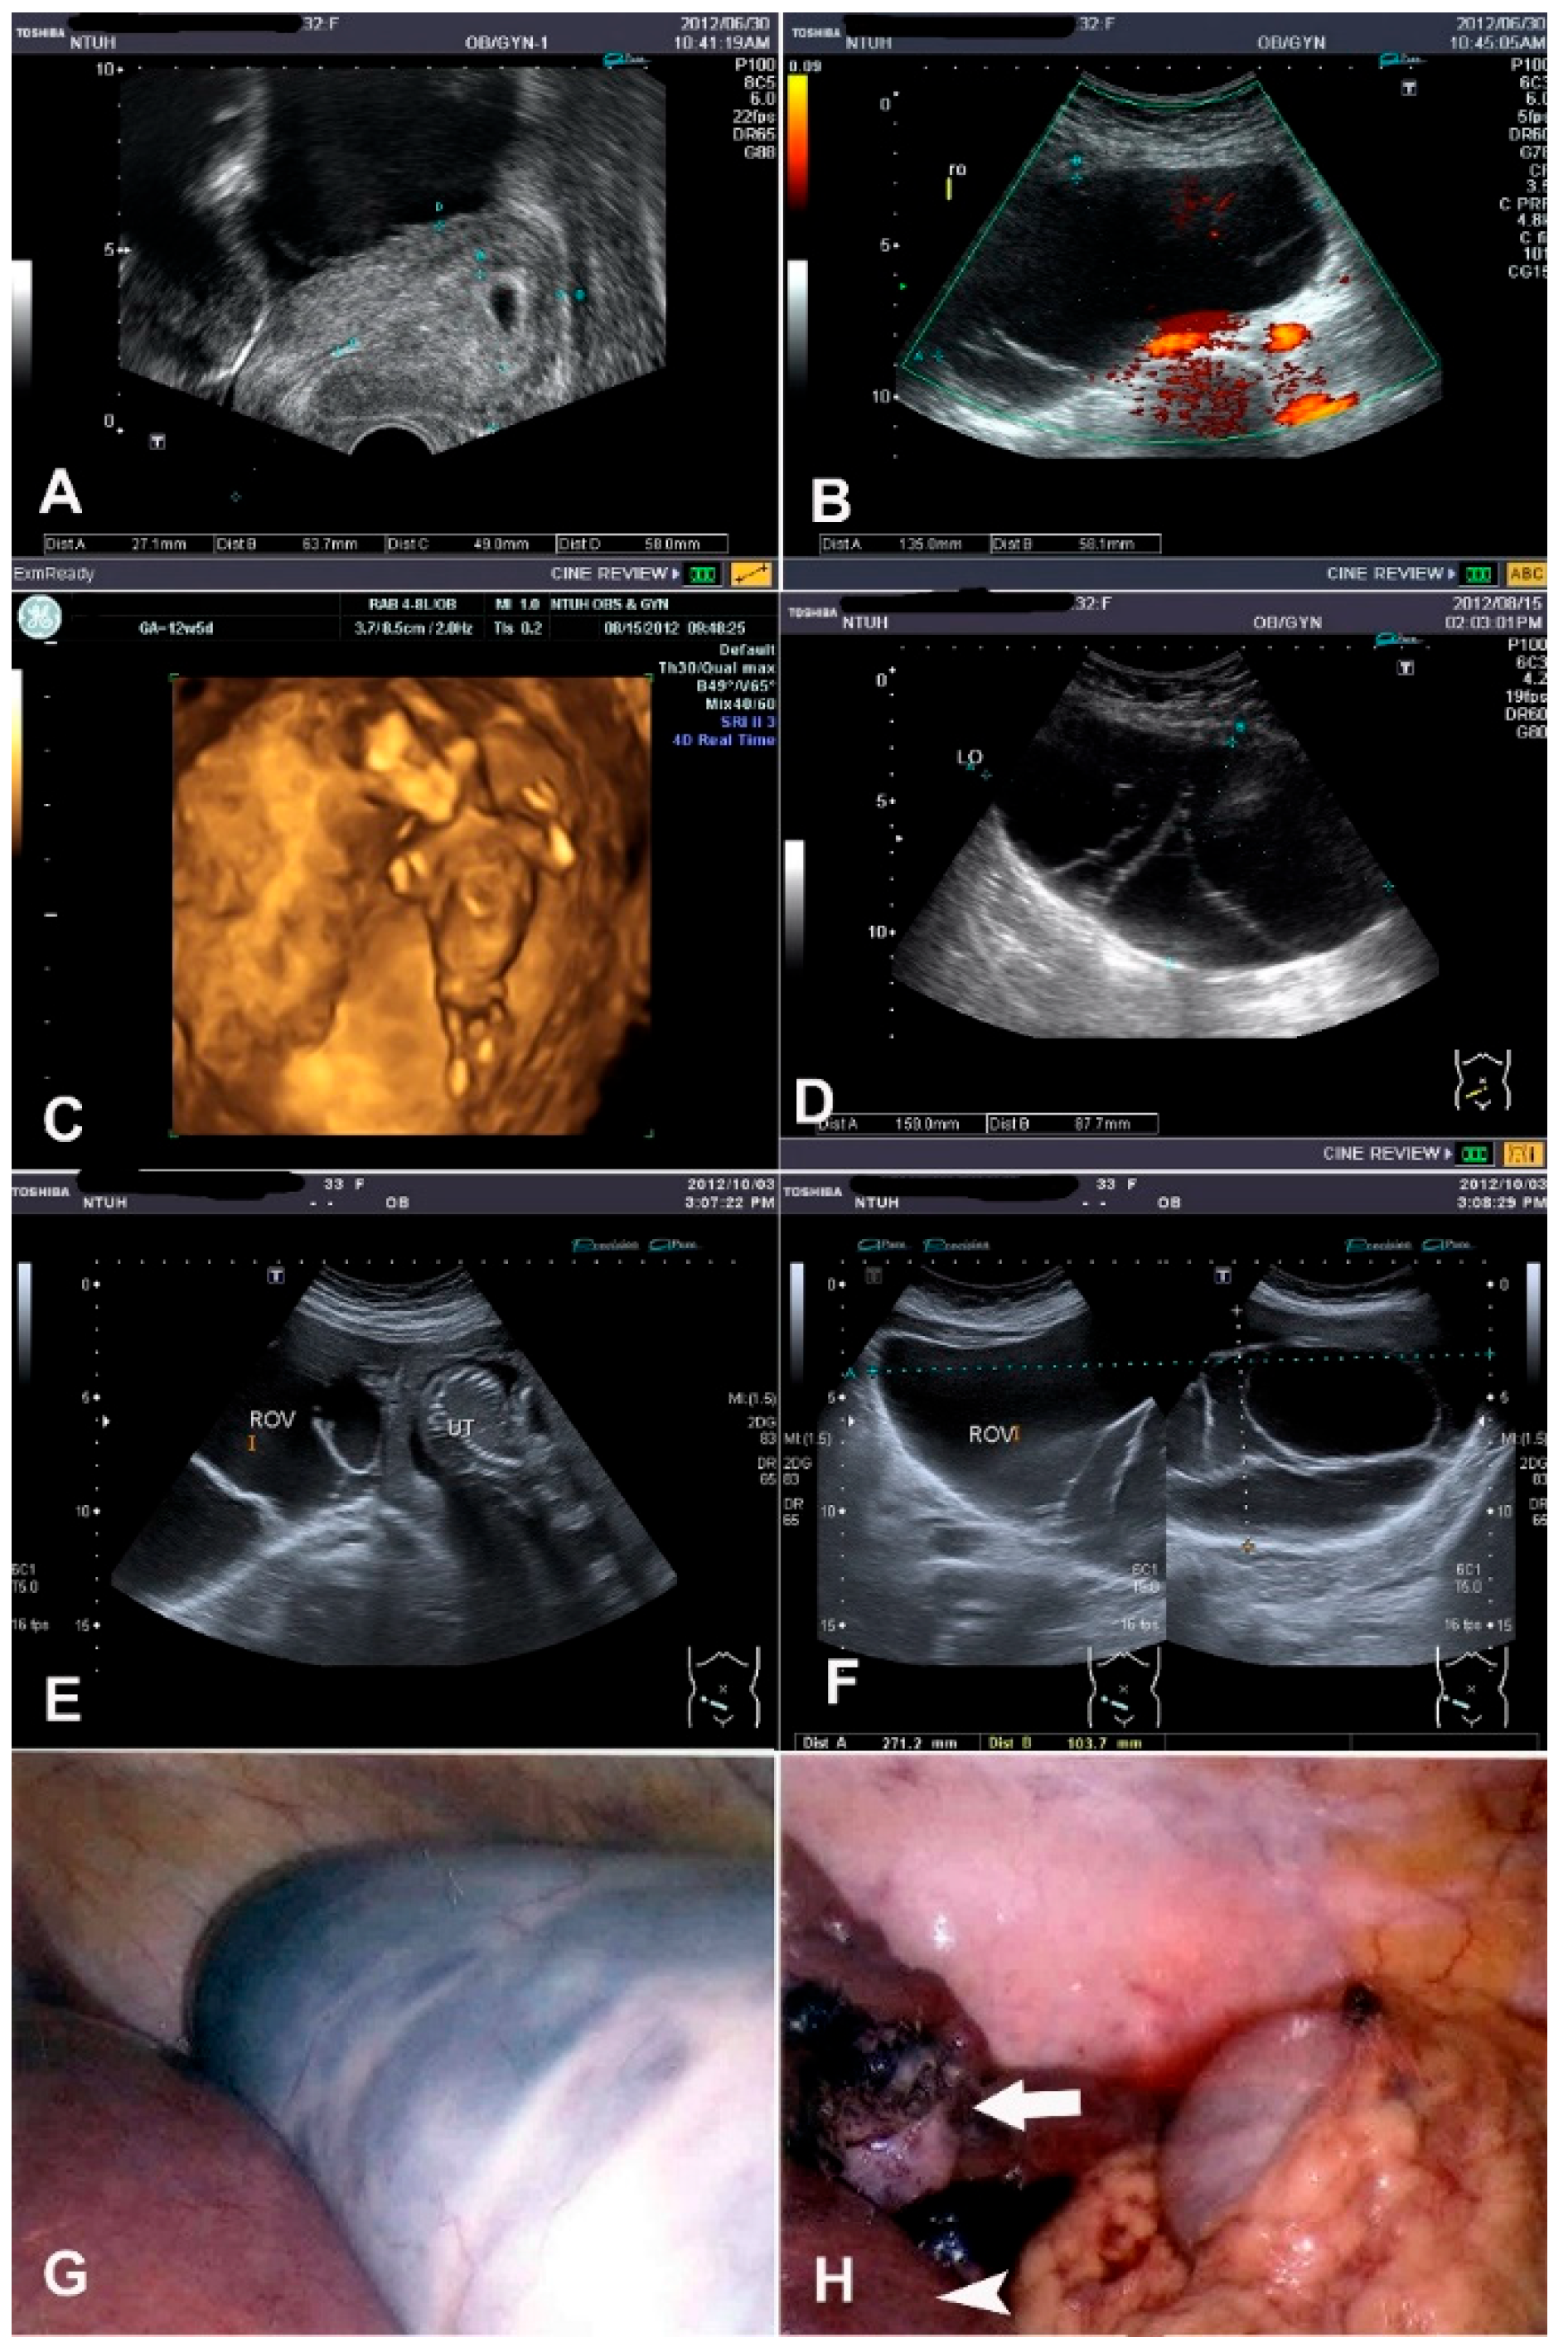

3.1.4. Case 4: Mucinous Tumor (GA of 21 Weeks)